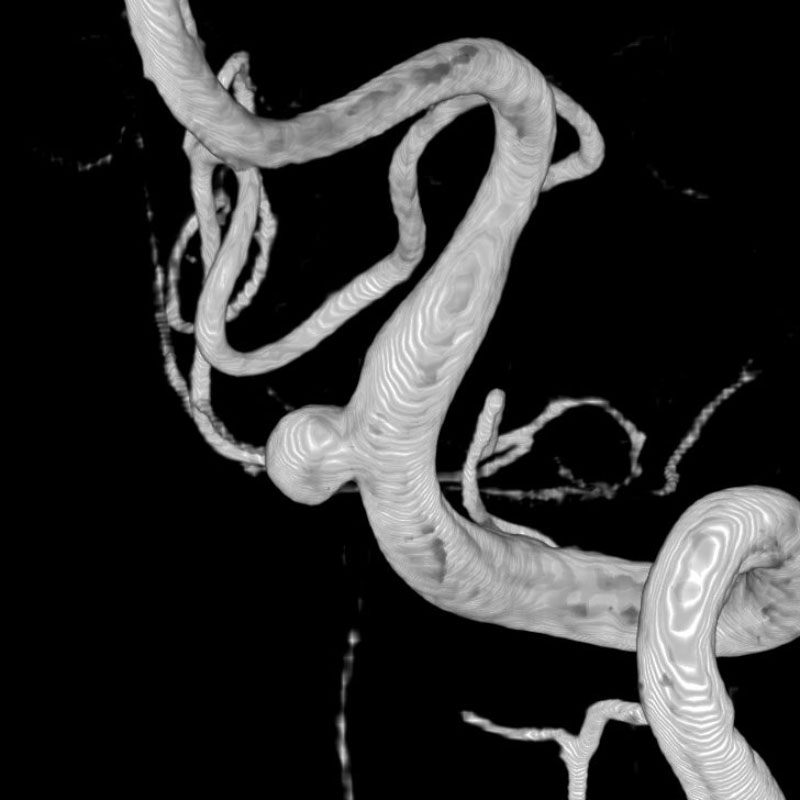

画像